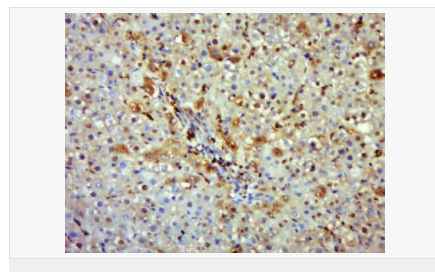

交叉反應(yīng):Human,Mouse,Rat(predicted:Dog,Pig,Horse,Sheep) 推薦應(yīng)用:WB,IHC-P,IHC-F,ICC,IF,Flow-Cyt

| 產(chǎn)品應(yīng)用 | WB=1:500-2000 IHC-P=1:100-500 IHC-F=1:100-500 Flow-Cyt=1μg/Test ICC=1:100-500 IF=1:100-500 (石蠟切片需做抗原修復(fù)) not yet tested in other applications. optimal dilutions/concentrations should be determined by the end user. |

| 產(chǎn)品介紹 | Nitric oxide (NO) is an inorganic, gaseous free radical that carries a variety of messages between cells. Vasorelaxation, neurotransmission and cytotoxicity can all be potentiated through cellular response to NO. NO production is mediated by members of the nitric oxide synthase (NOS) family. NOS catalyzes the oxidization of L-arginine to produce L-citrulline and NO. Two constitutive isoforms, brain or neuronal NOS (b or nNOS, type I) & endothelial cell NOS (eNOS, type III), and one inducible isoform (iNOS, type II), have been cloned. All NOS isoforms contain calmodulin, nicotinamide adenine dinucleotide phosphate (NADPH), flavin adenine dinucleotide (FAD), and flavin mononucleotide (FMN) binding domains. Nitric oxide synthase is expressed in liver, macrophages, hepatocytes, synoviocytes, stimulated glial cells and smooth muscle cells. Cytokines such as interferon-gamma (IFN), tumor necrosis factor (TNF), interleukin-1 and -2, and lipopolysaccarides (LPS) cause an increase in iNOS mRNA, protein, and activity levels. Protein kinase C-stimulating agents exhibit the same effect on iNOS activity. After cytokine induction, iNOS exhibits a delayed activity response which is then followed by a significant increase in NO production over a long period of time. Human iNOS is regulated by calcium/calmodulin (in contrast with mouse NOS2). Function: Produces nitric oxide (NO) which is a messenger molecule with diverse functions throughout the body. In macrophages, NO mediates tumoricidal and bactericidal actions. Also has nitrosylase activity and mediates cysteine S-nitrosylation of cytoplasmic target proteins such COX2. Subunit: Homodimer. Binds SLC9A3R1. Tissue Specificity: Expressed in the liver, retina, bone cells and airway epithelial cells of the lung. Not expressed in the platelets. Similarity: Belongs to the NOS family. Contains 1 FAD-binding FR-type domain. Contains 1 flavodoxin-like domain. SWISS: P35228 Gene ID: 4843 Database links: Entrez Gene: 4843 Human Entrez Gene: 18126 Mouse Omim: 163730 Human SwissProt: P35228 Human SwissProt: P29477 Mouse Unigene: 709191 Human Unigene: 2893 Mouse Unigene: 10400 Rat Important Note: This product as supplied is intended for research use only, not for use in human, therapeutic or diagnostic applications. 合成與降解(Synthesis and Degradation) 催化生物體內(nèi)一氧化氮(NO)生成的酶。分神經(jīng)型一氧化氮合成的酶(nNOS or NOS-1)、誘導(dǎo)型一氧化氮合成的酶(iNOS or NOS-2)、內(nèi)皮型一氧化氮合成的酶(eNOS or NOS-3)。 |